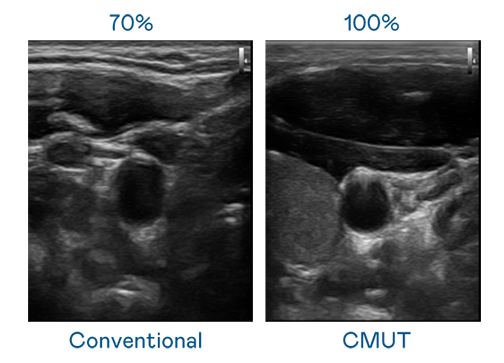

CMUT 技术是一种用电容式微机电元件来产生超音波讯号的技术。与传统 PZT 压电式技术相比,CMUT 频宽增加 30%,更宽频的超音波讯号让影像解析度大幅提升,是实现高影像品质医疗超音波扫描、促进精准医疗发展的关键技术。

大频宽带来超清晰影像

超音波影像的解析度高低,首先取决于探头能发出的讯号频宽。冰球突破 CMUT 可提供高清晰的超音波讯号,提供高频宽、高灵敏度、影像纹理细节更高的超音波影像,协助医护人员缩短影像判读时间及利用精准的医疗影像进行诊断。